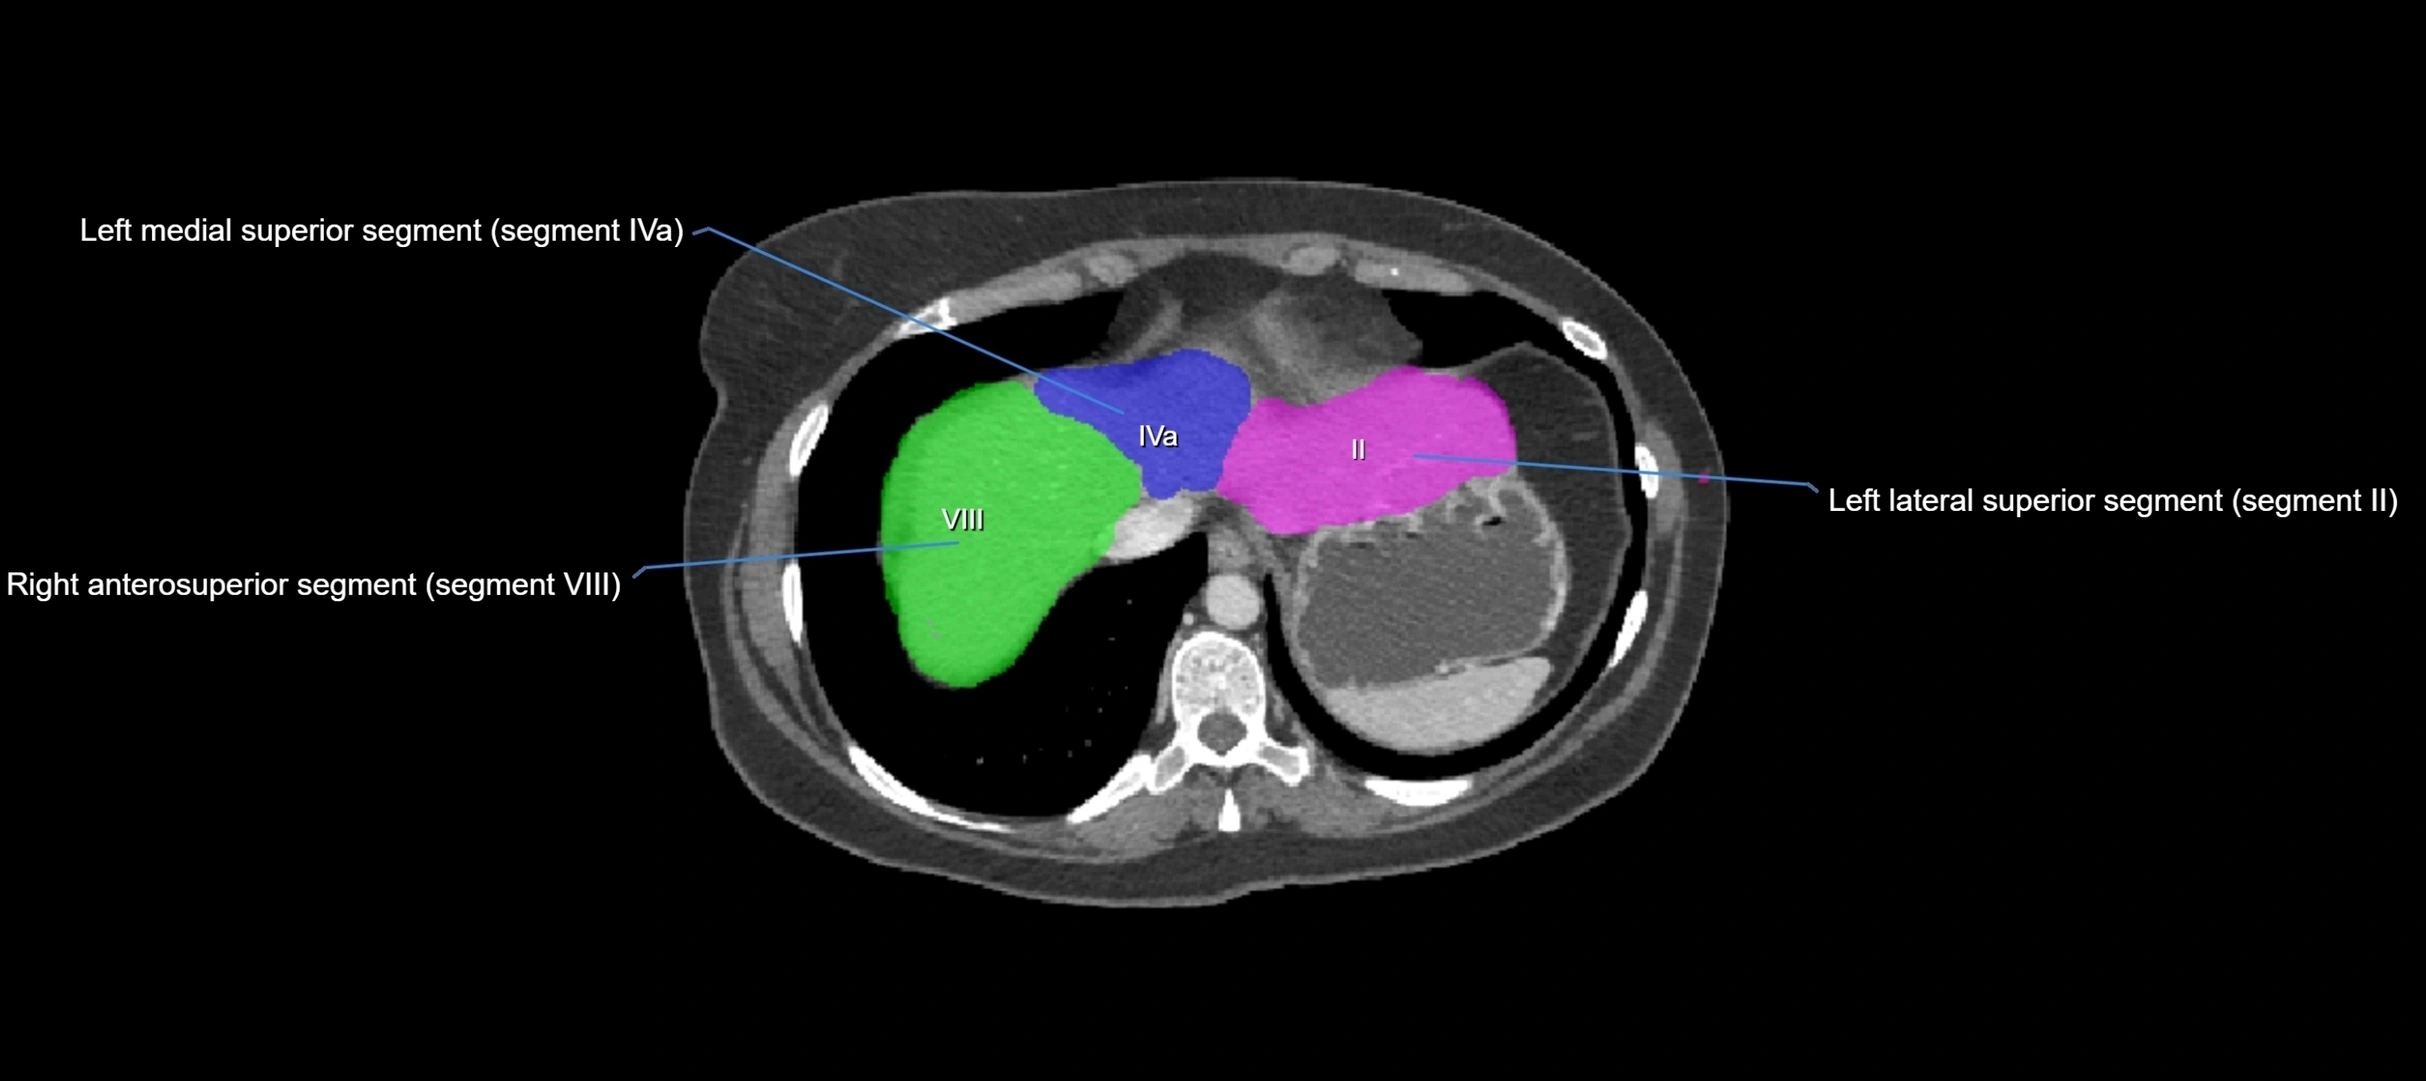

CT Image

image